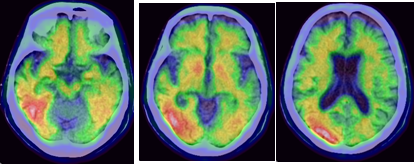

<그림. 치매환자의 알자뷰 영상>

올해 2월 한국 식약처는 알츠하이머 치매 진단제로 퓨쳐켐 알자뷰의 품목허가를 승인하였다. 2015년 6월부터 2016년 2월까지 106명의 임상 3상 시험을 통하여 MRI를 참고하지 않은 알자뷰를 육안적으로 분석하였을 때, 알츠하이머 치매 환자 진단 예민도가 91%, 특이도가 85%를 나타내어 기존의 약제와 유사한 효능을 나타내며 특별한 부작용이 나타나지 않았다. 미국 FDA의 승인을 받은 3개의 외국 의약품의 뒤를 이은 개발이며, 2008년 전구체 개발을 시작하였고, 2012년 부터 마이크로도싱 임상시험, 1상 임상시험등을 한걸음씩 진행시켜서 드디어 품목허가를 획득한 우리나라 핵의학의 쾌거이다. 신경학 연구에 따르면 알츠하이머병 환자의 이상을 시간의 흐름에 따라 영상으로 확인하면, 가장 먼저 아밀로이드 영상으로 환자 증상이 나타나기 전 대뇌의 아밀로이드 침착을 관찰할 수 있다가 증상이 조금씩 나타나기 시작하면서 타우 영상으로 확인이 가능하고, 증상이 심해지면 MRI에서도 대뇌 위축등이 나타날 수 있는 것으로 이해되고 있다. 그렇다며 알츠하이머병이 생기기 전 아밀로이드 영상으로 해당 환자가 향후 알츠하이머병이 나타날 것을 미리 알 수 있게 되는 것은 아닐까? 이것은 마치 타임머신을 가지고 미래에 가서 자신의 질병이 발생할 것을 확인하는 것과 유사한 획기적인 방법이 되지 않을까 기대가 된다.